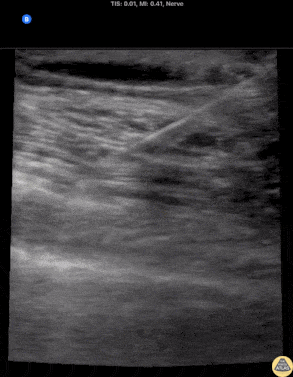

80s F presented with a mechanical fall, found to have multiple rib fractures and subsequent poor incentive spirometry. An in-plane serratus anterior plane block was performed on the affected side using the linear transducer in a transverse plane orientation at the level of the 4th/5th rib at the mid axillary line. Local anesthetic can be seen spreading in the fascial plane between serratus anterior (deep) and latissimus dorsi (superficial) muscles. The lung pleura can be seen sliding below serratus anterior. The patient reported relief soon after the block. Dr. Michael Heffler, PGY3 Denver Health Residency in Emergency Medicine